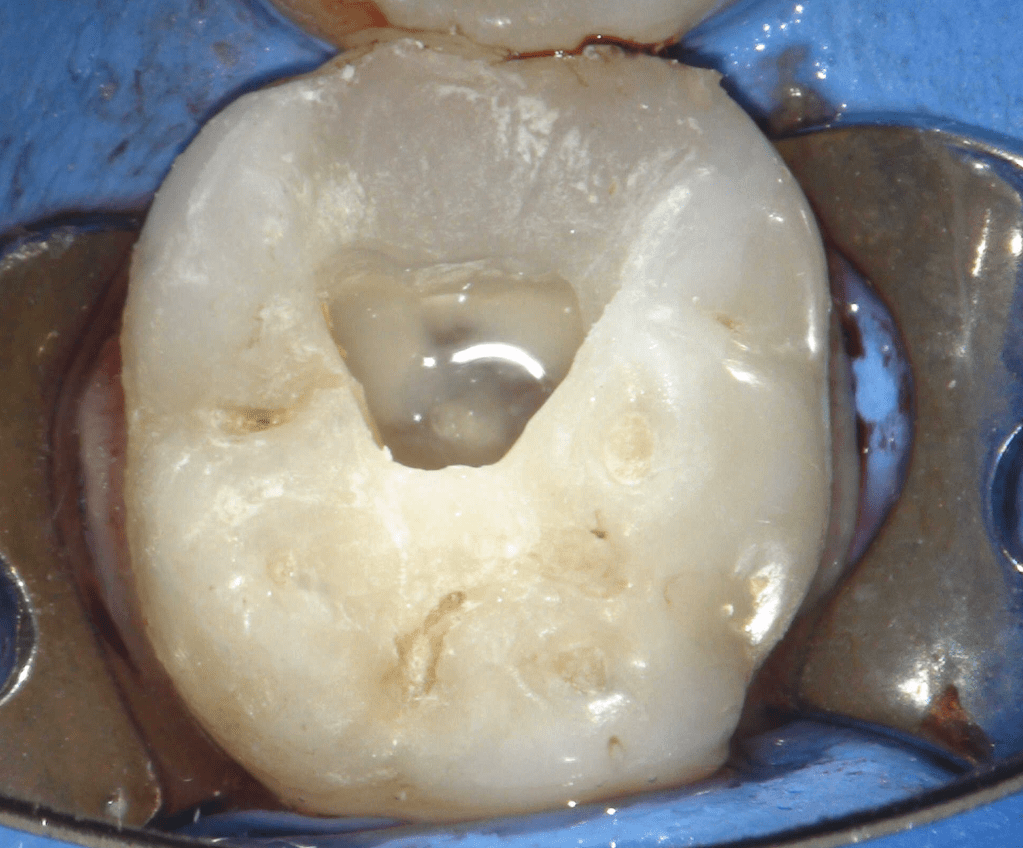

Reconstrucción preendodóntica

Reco preendo + 4 conductos molar superior